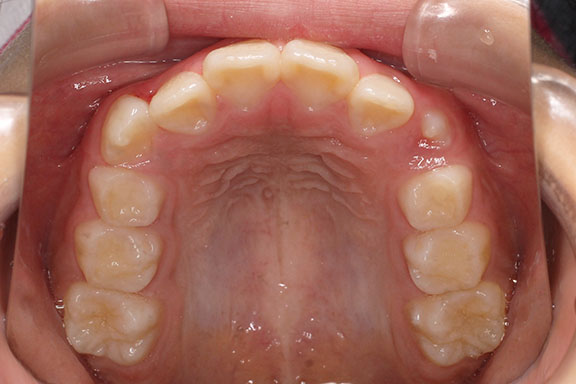

側方歯(犬歯、小臼歯)の生え変わりの時期。 前歯のがたつきを気にされ、小児矯正からの治療を希望されました。 お母様は、矯正治療経験済みですので、治療には前向きで早期治療の必要性を納得されていました。 小児矯正では、永久歯の生え変わるためのスペースを増加させ、がたつきを軽減させることを目的で行います。 残ったがたつきは、全ての永久歯が生え変わってから、本格矯正(マルチブラケット装置での治療)で改善しています。 比較的、叢生量は少ないため、本格矯正は非抜歯にて配列しました。

マルチブラケット 動的治療期間 2年6か月 調整回数16回 特に問題もなく、保定後も安定しています。